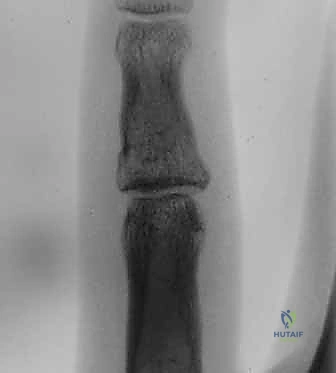

2. التصوير بالأشعة السينية (X-Rays)

هو المعيار الذهبي الأولي. يجب أخذ صور شعاعية واضحة ومحددة للإصبع المصاب (وليس لليد بأكملها) في ثلاث وضعيات:

* الوضعية الأمامية الخلفية (AP): لتقييم المحور الجانبي للإصبع والبحث عن شقوق عظمية.

* الوضعية الجانبية الحقيقية (True Lateral): هي الصورة الأهم على الإطلاق. من خلالها يتم تحديد حجم القطعة العظمية المكسورة، ومقدار انزياح المفصل. يبحث الجراح الماهر هنا عن علامة "V-Sign" الشهيرة، والتي تدل على عدم تطابق الأسطح المفصلية ووجود خلع جزئي غير مستقر.

* الوضعية المائلة (Oblique): تساعد في رؤية تفاصيل الكسور المفتتة التي قد تختفي في الوضعيات الأخرى.